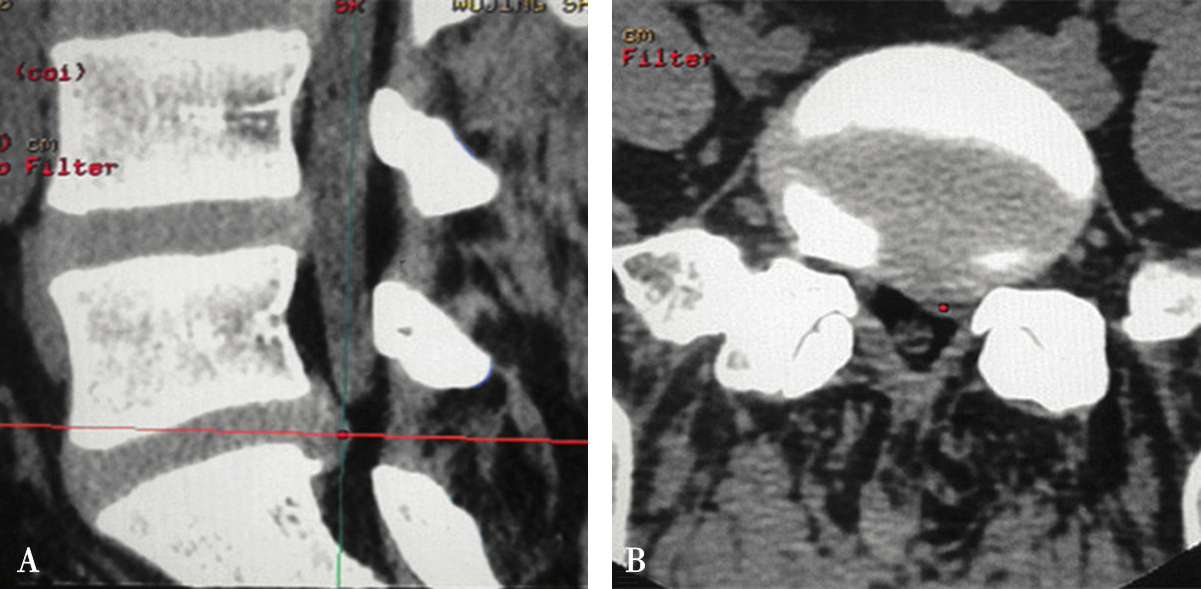

图3-3-9 机架平行椎间隙扫描

A.沿椎间隙轴线扫描(红坐标线);B.横断位层面多有椎板阻挡

在扫描产生的多层横断面中选择出最符合穿刺要求的一层,作为设计入路和引导穿刺定位的操作平面,我们将该层称为“靶点操作平面”。根据不同的手术目的选择该平面的要求也不同:避骨入路类手术如经椎板间入路椎间盘靶点定位类,应选择具有最大程度避开神经、血管、脏器、骨质而到达靶点的平面,如图3-3-12中显而易见图B是最合适的平面;经椎间隙侧方入路时的扫描图像中(图3-3-13),图B最合适;而经骨入路类手术如经皮椎体骨折复位外固定、椎体成形术等,应选择椎弓根宽大处的平面,如图3-3-14中图B作为操作平面最合适。CT机架角度扫描的横断位平面自然也是倾斜的,而穿刺定位入路是在该平面内的,因此存在如下关系:CT机架扫描角度=靶点操作平面角度=定位针穿刺时的头足倾斜角度(图3-3-15)。

图3-3-14 沿椎弓根轴线扫描的不同层

A.椎弓根偏头侧平面;B.椎弓根中间平面;C.椎弓根偏足侧平面